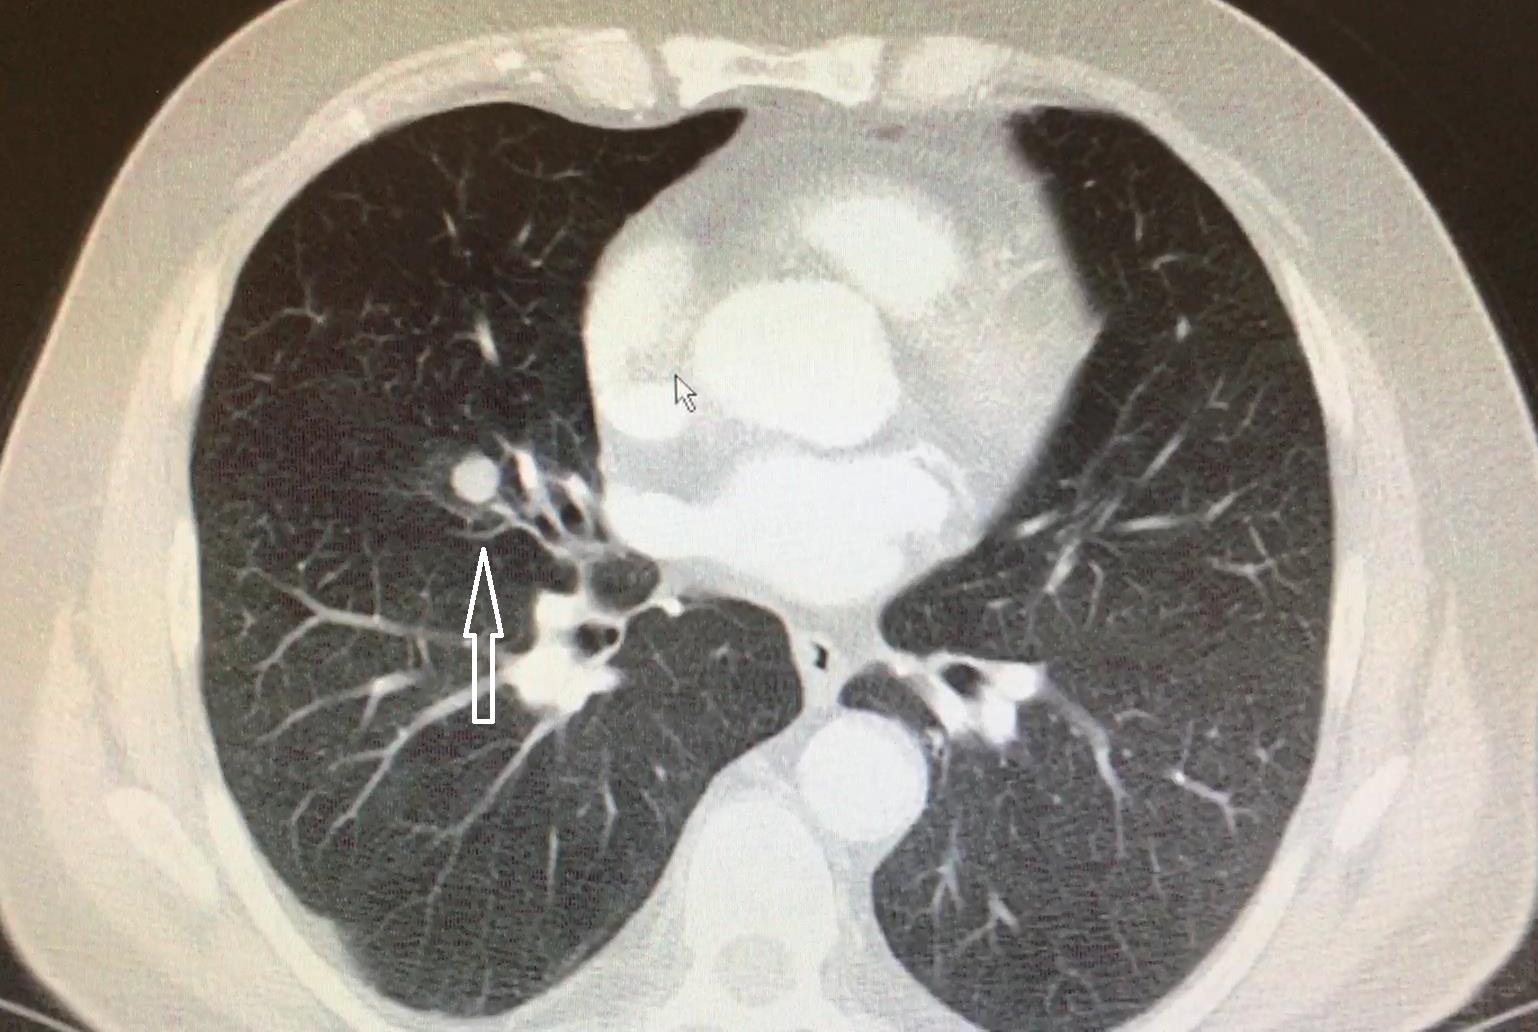

Akcigerinizde Nodul Saptandi Peki Simdi Ne Olacak

Akciger Nodullerini Ihmal Etmeyin

Akciger Nodulu Tam Olarak Nedir Sagliga Bir Adim

Akciger Nodulu Belirtileri Ve Tedavisi Akciger Gen Tr

Akcigerde Nodul Nedir Belirtileri Nedenleri Bitkisel Tedavisi